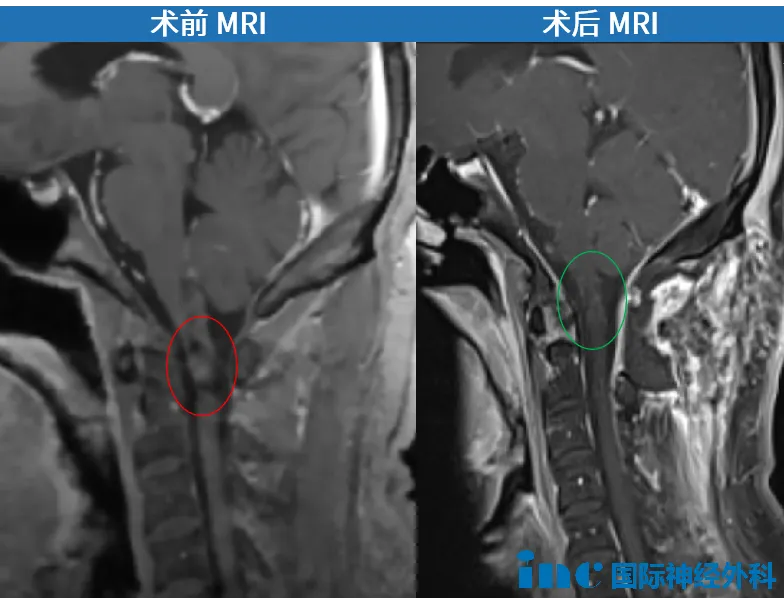

巴教授仔细分析了郑先生的影像后,给出了明确答复:“影像显示了位于C1颈髓内的一个海绵状血管畸形此前导致了一次内生性出血,进而向上扩展到延髓下部。实际上,导致最初出血的根本原因是位于脊髓右侧的血管畸形。

但手术切除技术上完全可行。我知道如何安全暴露病灶,虽然不是紧急手术,但结合你之前的出血情况,尽早切除才能避免后续风险。”同时,教授也坦诚:“之前出血已损伤部分神经,术后症状可能不会完全消失,但会有改善。”

10月2日,手术正式开始。无影灯下,巴教授主刀,中国团队密切配合,每一步操作都小心翼翼。经过数小时的奋战,手术顺利完成。

术后第1天,郑先生就顺利转出ICU。术后部分功能也在好转。